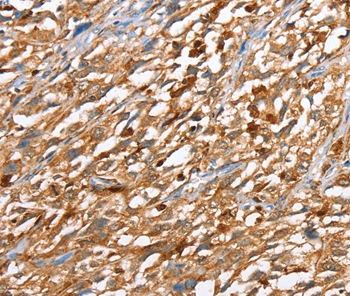

Immunohistochemical analysis of paraffin-embedded Human esophagus cancer tissue using #36027 at dilution 1/40.